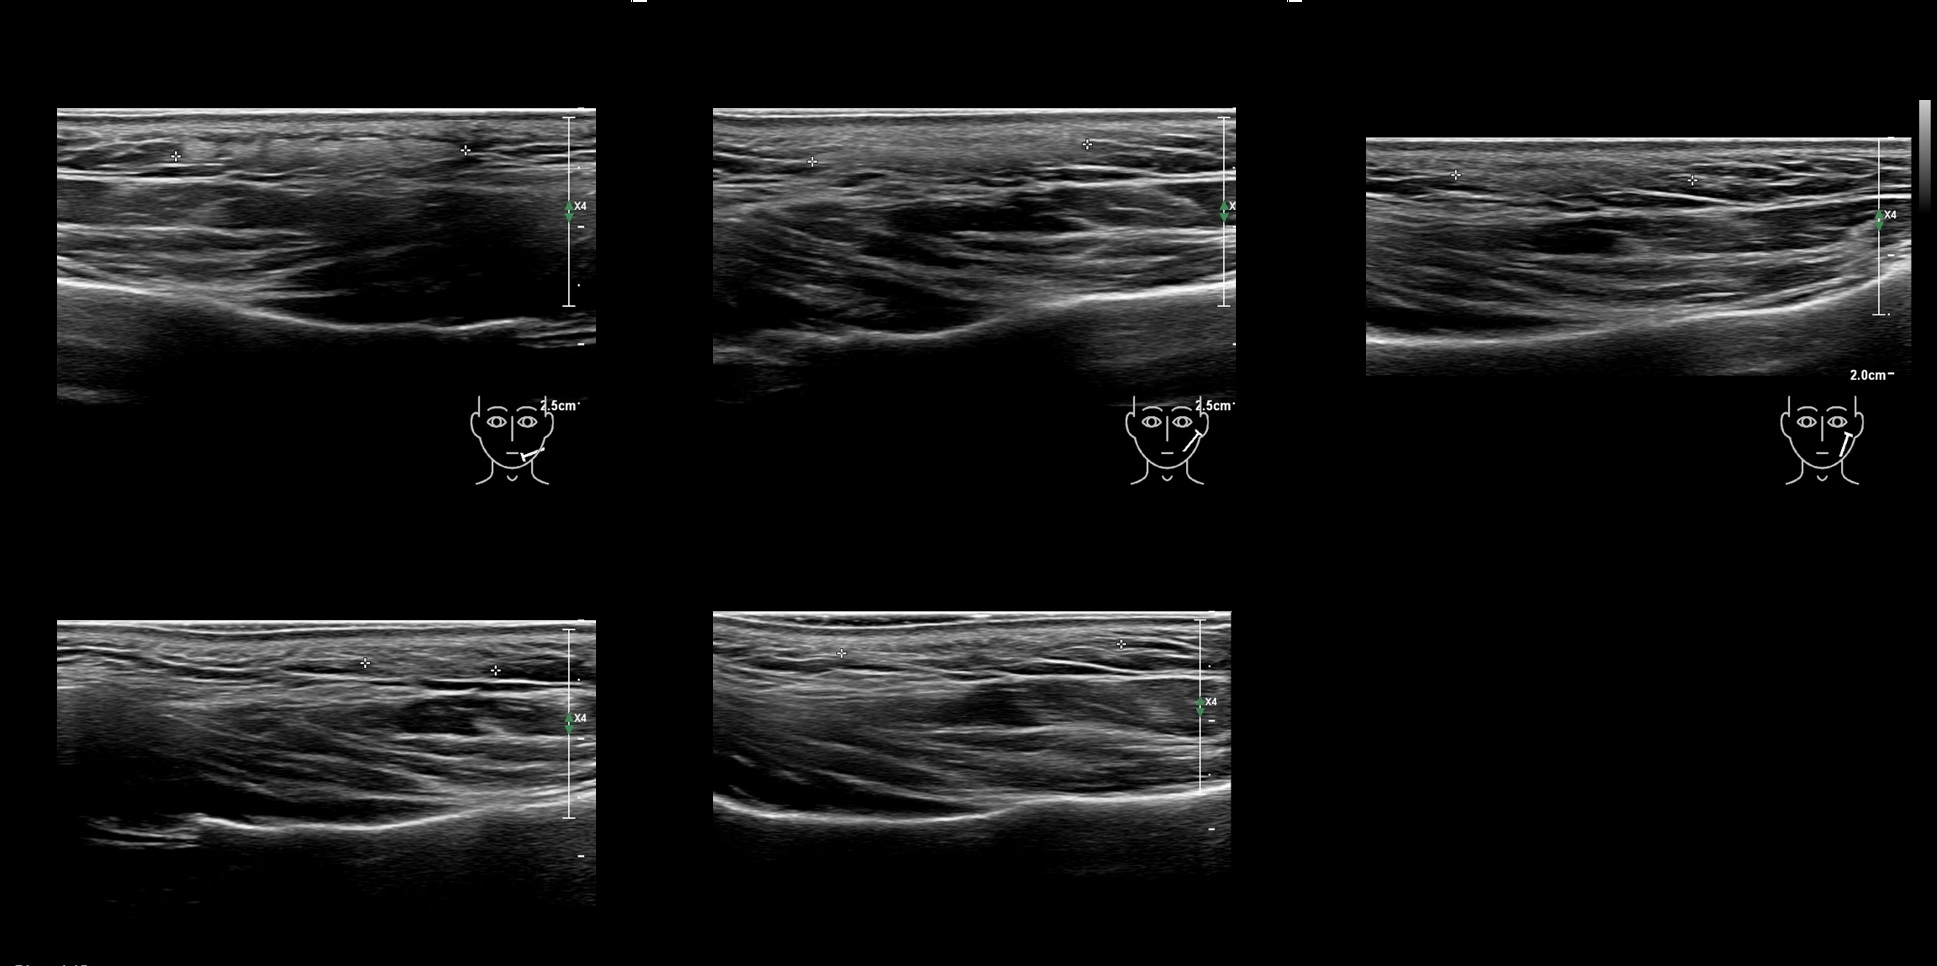

Fillers

Draw in the image on the right where the fillers are located. To check if your answer is correct, please click on the secondary image.